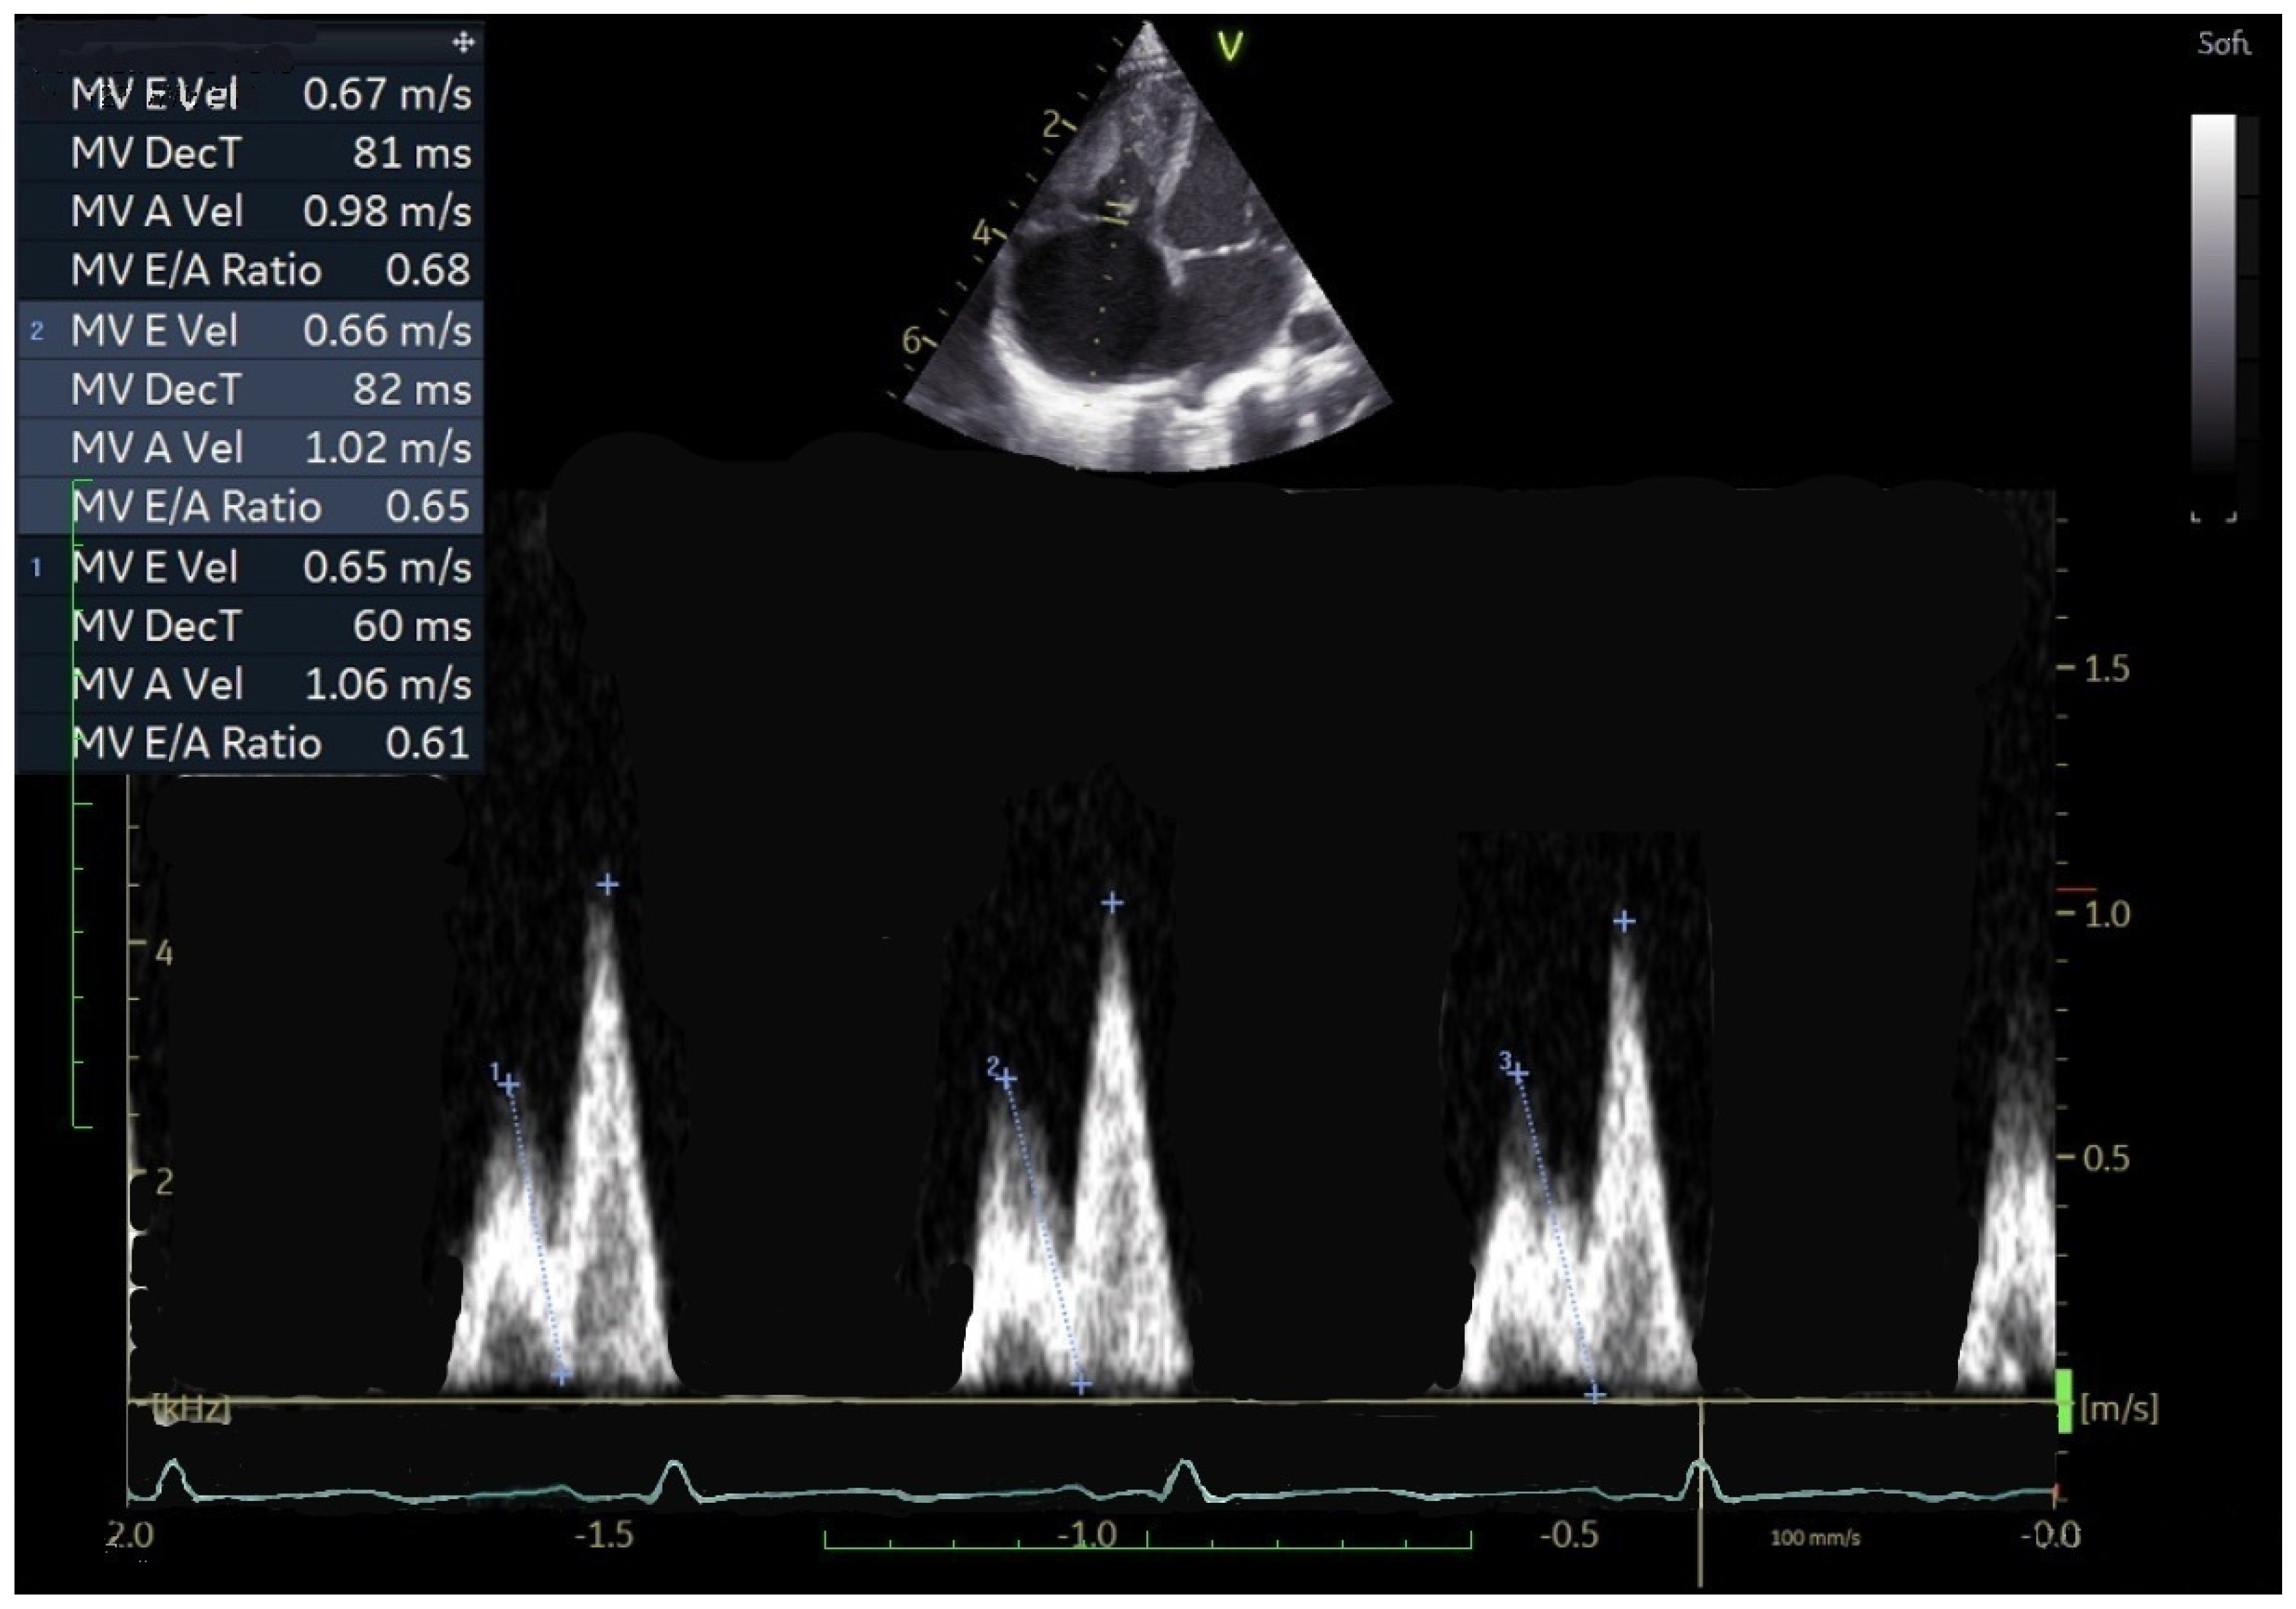

3.3. Patterns of TV Inflow in Children with CHD

- Cantinotti, M.; Marchese, P.; Scalese, M.; Franchi, E.; Assanta, N.; Koestenberger, M.; Van den Eynde, J.; Kutty, S.; Giordano, R. Normal Values and Patterns of Normality and Physiological Variability of Mitral and Tricuspid Inflow Pulsed Doppler in Healthy Children. Healthcare 2022, 10, 355. [Google Scholar] [CrossRef]

- Cantinotti, M.; Lopez, L. Nomograms for Blood Flow and Tissue Doppler Velocities to Evaluate Diastolic Function in Children: A Critical Review. J. Am. Soc. Echocardiogr. 2013, 26, 126–141. [Google Scholar] [CrossRef]

- Harada, K.; Takahashi, Y.; Shiota, T.; Suzuki, T.; Tamura, M.; Ito, T.; Takada, G. Effect of Heart Rate on Left Ventricular Diastolic Filling Patterns Assessed by Doppler Echocardiography in Normal Infants. Am. J. Cardiol. 1995, 76, 634–636. [Google Scholar] [CrossRef]

| E veloc cm/s | 0.58 ± 0.39 | 0.59 ± 0.19 | 0.221 | 0.60 ± 0.14 | 0.68 ± 0.20 | 0.101 | 0.60 ± 0.22 | 0.63 ± 0.19 | 0.382 |

| A vel cm/s | 0.62 ± 0.13 | 0.92 ± 0.28 | <0.001 | 0.61 ± 0.16 | 0.78 ± 0.26 | 0.02 | 0.61 ± 0.15 | 0.87 ± 0.28 | <0.001 |

| E DT ms | 86.7 ± 29.1 | 79.6 ± 27.2 | 0.364 | 97.8 ± 31.5 | 87.5 ± 21.4 | 0.161 | 95.5 ± 31.2 | 82.7 ± 25.1 | 0.010 |

| E/A | 1.12 ± 1.50 | 0.66 ± 0.15 | 0.004 | 1.08 ± 0.42 | 0.88 ± 0.18 | 0.128 | 1.09 ± 0.79 | 0.75 ± 0.20 | <0.001 |